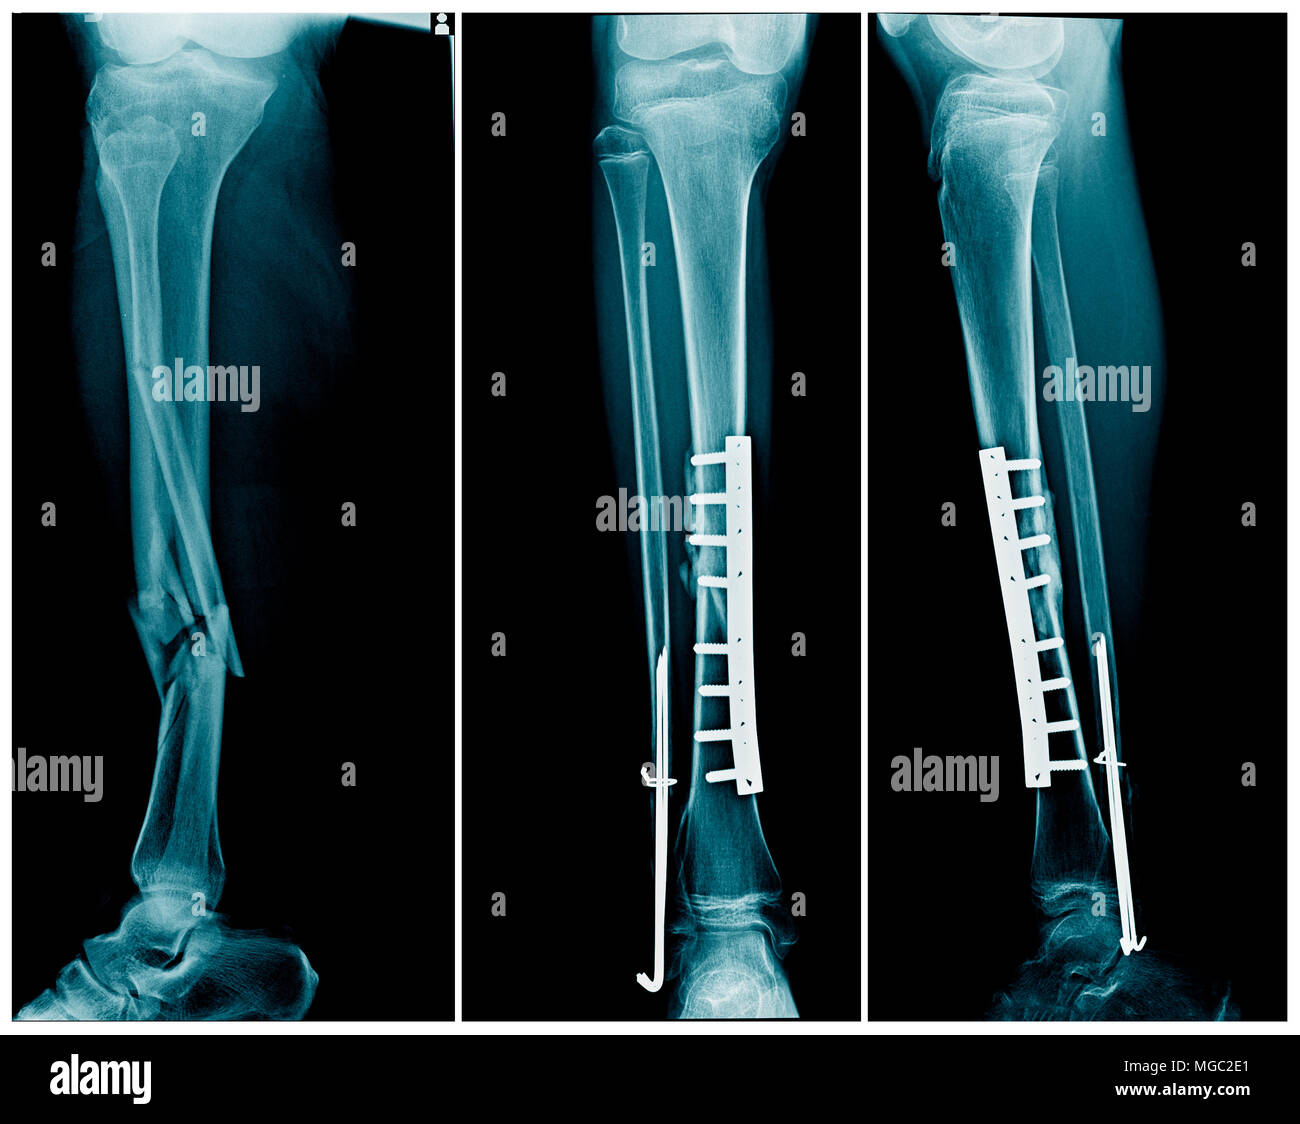

There are three basic types of external fixators: standard uniplanar fixator, ring fixator, and hybrid fixator. The numerous devices used for internal fixation are roughly divided into a few major categories: wires, pins and screws, plates, and intramedullary nails or rods.

External Fixation

External fixation involves placing metal pins or screws into the bone on either side of the fracture and then connecting these pins with an external frame. This method is often used for complex or open fractures when there is a risk of infection, swelling, or when internal fixation isn't feasible.

External fixation is a process for fracture fixation by which pins or wires are inserted into bone percutaneously and held together via an external scaffold. Initially described by Malgaigne in 1853, external fixation was proposed as an alternative to immobilization in plaster cast, traction, or internal fixation.

External fixator types divide into several different subcategories, including uniplanar, multiplanar, unilateral, bilateral, and circular fixators. By adding pins in different planes (i.e., placed perpendicular to each other), one can create a multiplanar construct. Uniplanar fixation devices are fast and easy to apply but are not as sturdy as multiplanar fixation. Bilateral frames are created when the pins are on both sides of the bone and can also add additional stability.